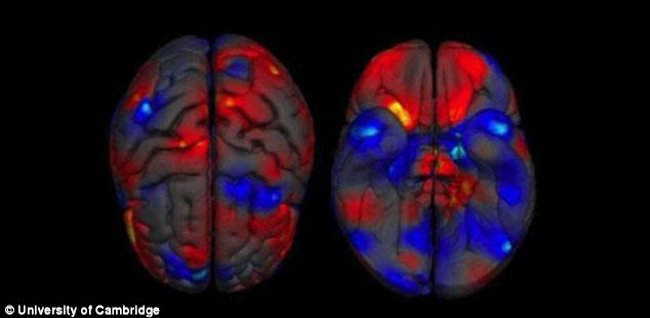

Nghiên cứu chỉ ra rằng: "Não bộ của nam giới và nữ giới không khác nhau nhiều". Các nhà nghiên cứu đã tìm ra sự khác biệt về mặt cấu trúc giữa não bộ của nam giới và nữ giới nhưng họ không thể xác định giới tính cá nhân mà chỉ dựa vào hình chụp MRI của bộ não như hình bên dưới.

Vì vậy, trong một nghiên cứu gần đây nhất, các nhà khoa học thần kinh hành vi đứng đầu là Daphna Joel tại trường đại học Tel Aviv ở Israel đã hướng dẫn các thành viên trong nhóm cùng cố gắng hoàn thiện nhiều nhất có thể. Bằng việc sử dụng những hình ảnh MRI sẵn có về bộ não con người, họ đo khối lượng chất xám (nhiều node thần kinh liên kết với nhau, là điểm trung tâm của các tế bào thần kinh) và chất trắng (một nhóm sợi thần kinh truyền các tín hiệu cho hệ thần kinh) trong số hơn 1400 bộ não của con người. Họ cũng nghiên cứu dữ liệu từ hình ảnh khuếch tán tensor đưa ra cách làm thế nào để những chất trắng kéo dài trong não và kết nối với các khu vực khác.

Nhóm nghiên cứu đã tìm thấy một số cấu trúc khác biệt giữa nam và nữ. Ví dụ như: Hippocampus (hồi hải mã) trái là khu vực nằm bên trong não liên quan đến trí nhớ và của nam giới thường lớn hơn nữ giới. Tuy nhiên, trong mỗi khu vực lại có khá nhiều sự chồng chéo lên nhau, ví dụ: một số phụ nữ lại có Hippocampus trái to hơn hoặc rất giống nam giới, trong khi đó một số Hippocampus của nam giới lại nhỏ hơn so với độ lớn trung bình của phụ nữ.

Nhóm nghiên cứu đã đăng tải trực tiếp trên trang Proceedings of the National Academy of Sciences rằng: "Phần lớn các bộ não là một khảm các cấu trúc của nam và nữ". Phụ thuộc vào việc các nhà nghiên cứu có nhìn thấy được chất xám, chất trắng hay dữ liệu hình ảnh khuếch tán tensor hay không. Có khoảng 23% và 53% bộ não có chứa hỗn hợp các vùng nằm ở khu vực cuối quang phổ ở cả nam và nữ. Rất ít - chỉ khoảng 0% đến 8% - bộ não có chứa toàn bộ cấu trúc riêng của nam giới và nữ giới". Joel nói: "Không có một đặc điểm riêng đặc thù nào về bộ não của nam và bộ não của nữ".